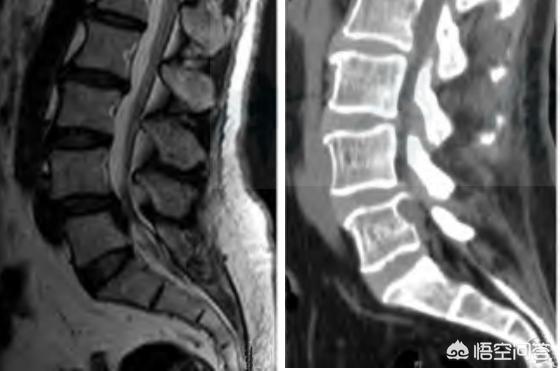

二次性脊柱管狭窄症による腰椎椎間板ヘルニアは、手術の理由にはなりませんが、両下肢に対称的な症状でない限り、腰椎椎間板ヘルニアに応じて治療することができ、CTやMRIを撮ることが原因で脊柱管狭窄症の不安、突出物が大きいことが判明していない、それらのほとんどは、脊柱管の狭窄を伴っている、あなたは保存的にすることができます!

腰部脊柱管狭窄症は、腰部脊柱管や椎間孔が狭窄し、馬尾や神経根を圧迫する病態であり、主な症状は腰背部痛や坐骨神経痛で、しばしば間欠性跛行症状を伴う。脊柱管の中心径が10mm以下を絶対狭窄、10~13mmを相対狭窄、外側伏在窩の前後径が3mm以下を狭窄とする。

腰椎椎間板ヘルニアの病態は、腰椎椎間板(髄核、線維輪、軟骨板で構成)の変性によるもので、線維輪が部分的または完全に破裂し、髄核が突出して神経根や馬尾を刺激・圧迫する症候群であり、脊椎の変性疾患として臨床上よく見られる疾患です。主に腰痛、坐骨神経痛、下肢のしびれ、馬尾症候群などの症状が現れます。